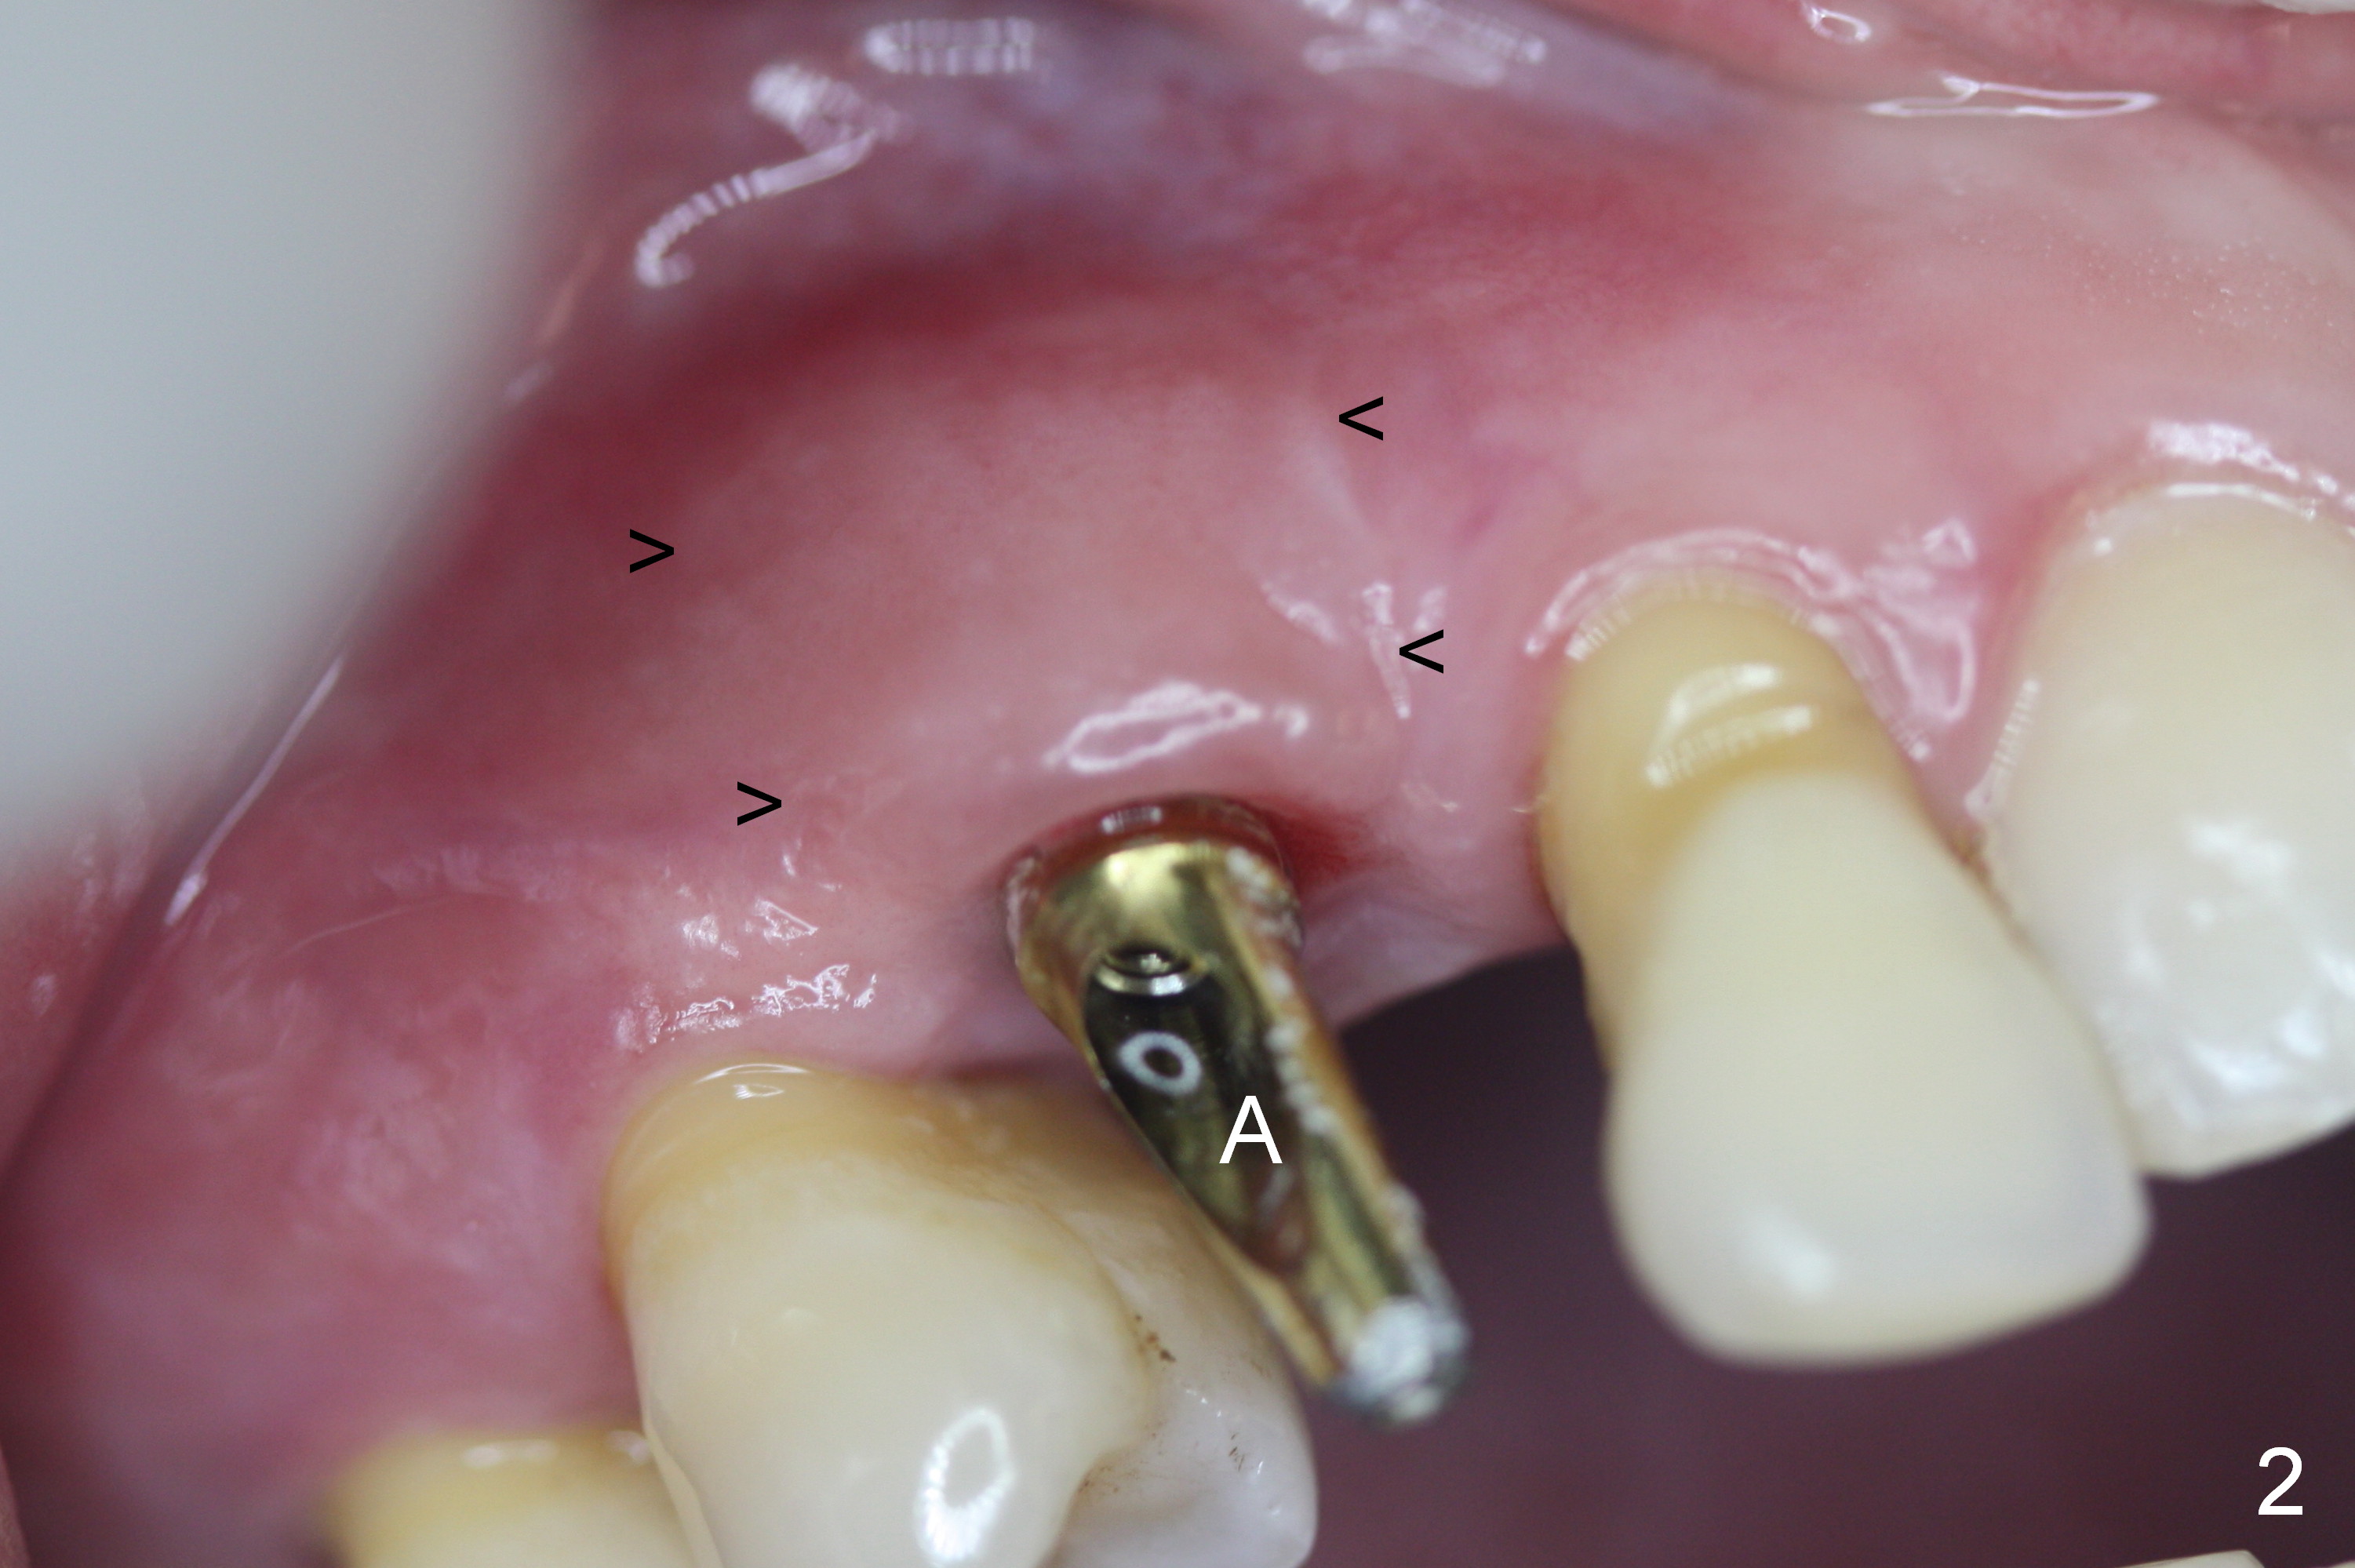

Four months post implant placement, the immediate provisional (Fig.1 P) has mobility with tenderness and perforation at the cervix (^). When the provisional is removed, the buccal plate bulging is more evident (Fig.2 arrowheads). The latter is apparently caused by bone expansion associated with implant placement (Fig.3 black *), since the bulging is not so obvious in a preop CBCT 3 D image (Fig.4 *). There is a layer of fiber granulation tissue (Fig.3 white *) around the mobile implant (I). More fiber tissue is noted when the implant is removed (Fig.5). A new osteotomy is created in the palatal wall of the existing implant site with 2 mm pilot drill, followed by 2.5 and 3 mm reamers. As a 4.5x17 mm tap is being inserted (Fig.6 T), it is deviated buccally. Reamers are re-used to try to remove more palatal bone to let the implant be placed more palatally. When a 4.5x17 mm tissue-level implant is placed (Fig.7,8 I with insertion torque >60 Ncm), there is a small buccal gap (Fig.8 *). A 20° angled abutment (Fig.7,8 A) is placed. An immediate provisional is fabricated with cosmetic satisfaction.

The gingiva is healthy 6 months postop (Fig.13) without buccal plate collapse (Fig.14). The implant and abutment have been prep for final restoration (Fig.15). Although the buccal plate is thin 3 years 5 months post cementation (Fig.16 B), the crest (>) is present, which accounts for no periimplantitis.